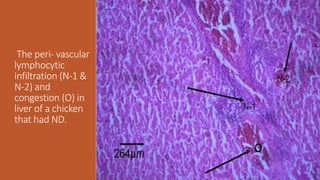

The peri- vascular

lymphocytic

infiltration (N-1 &

N-2) and

congestion (O) in

liver of a chicken

that had ND.